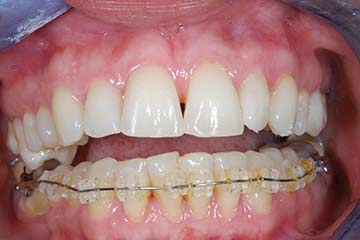

Riabilitazione gnatologica, ortodontica ed estetica

Durata del trattamento: un anno